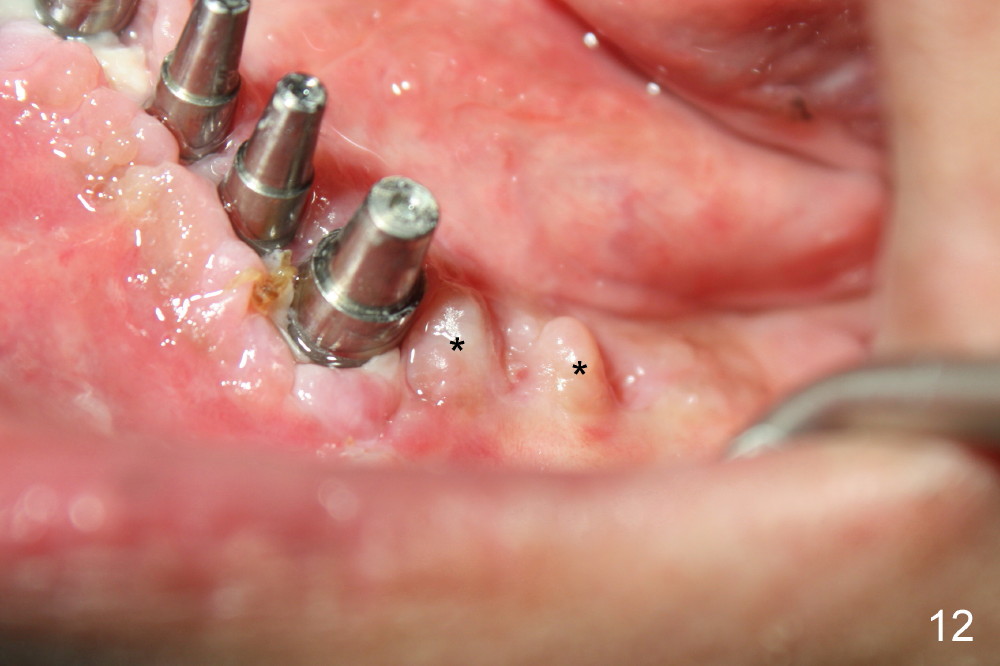

Once the patient improves oral hygiene as instructed, the wound around the implants begins to heal (Fig.10,11) one week later, while that continues healing around guided tissue regeneration area (Fig.12).